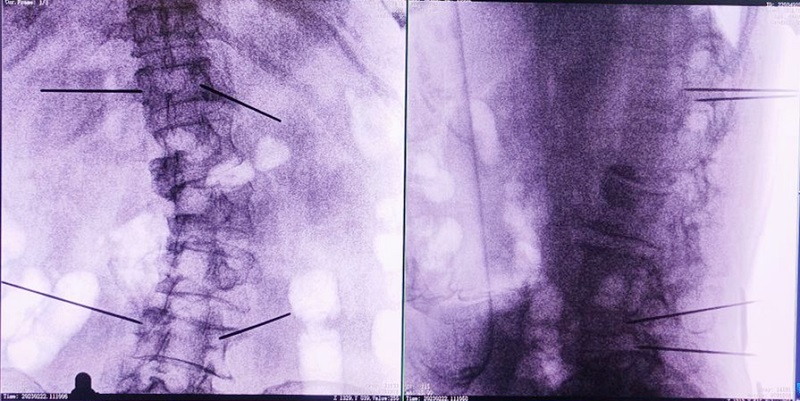

骨科手術(shù)機(jī)器人輔助下椎體成形術(shù),是以手術(shù)機(jī)器人智能機(jī)械臂為基礎(chǔ),仿照經(jīng)皮骨水泥椎體成形術(shù)的施術(shù)步驟,限定穿刺點(diǎn)、穿刺方向、角度和深度,使穿刺針經(jīng)過安全路徑進(jìn)入目標(biāo)區(qū)域,然后進(jìn)行骨水泥注入,輔助手術(shù)設(shè)計(jì)、精準(zhǔn)指導(dǎo)手術(shù)實(shí)施。以普愛醫(yī)療的骨科手術(shù)機(jī)器人為例,其輔助進(jìn)行的一例胸腰椎壓縮性骨折經(jīng)皮椎體成形術(shù)的過程如下:

(1)首先使用普愛醫(yī)療三維C形臂采集胸腰椎病灶三維圖像,對(duì)傷椎進(jìn)行三維重建;

(2)醫(yī)生制定個(gè)性化的手術(shù)方案,在機(jī)器人導(dǎo)航界面上進(jìn)行路徑規(guī)劃;

(3)根據(jù)設(shè)定好的的位置和入針方向,植入引導(dǎo)針;

(4)所有引導(dǎo)針植入完畢后,沿引導(dǎo)針方向進(jìn)行椎弓根及椎體置管,建立通道;

(5)沿通道注入骨水泥,恢復(fù)椎體高度,并觀察其擴(kuò)散情況,達(dá)到滿意效果后,停止注入骨水泥。